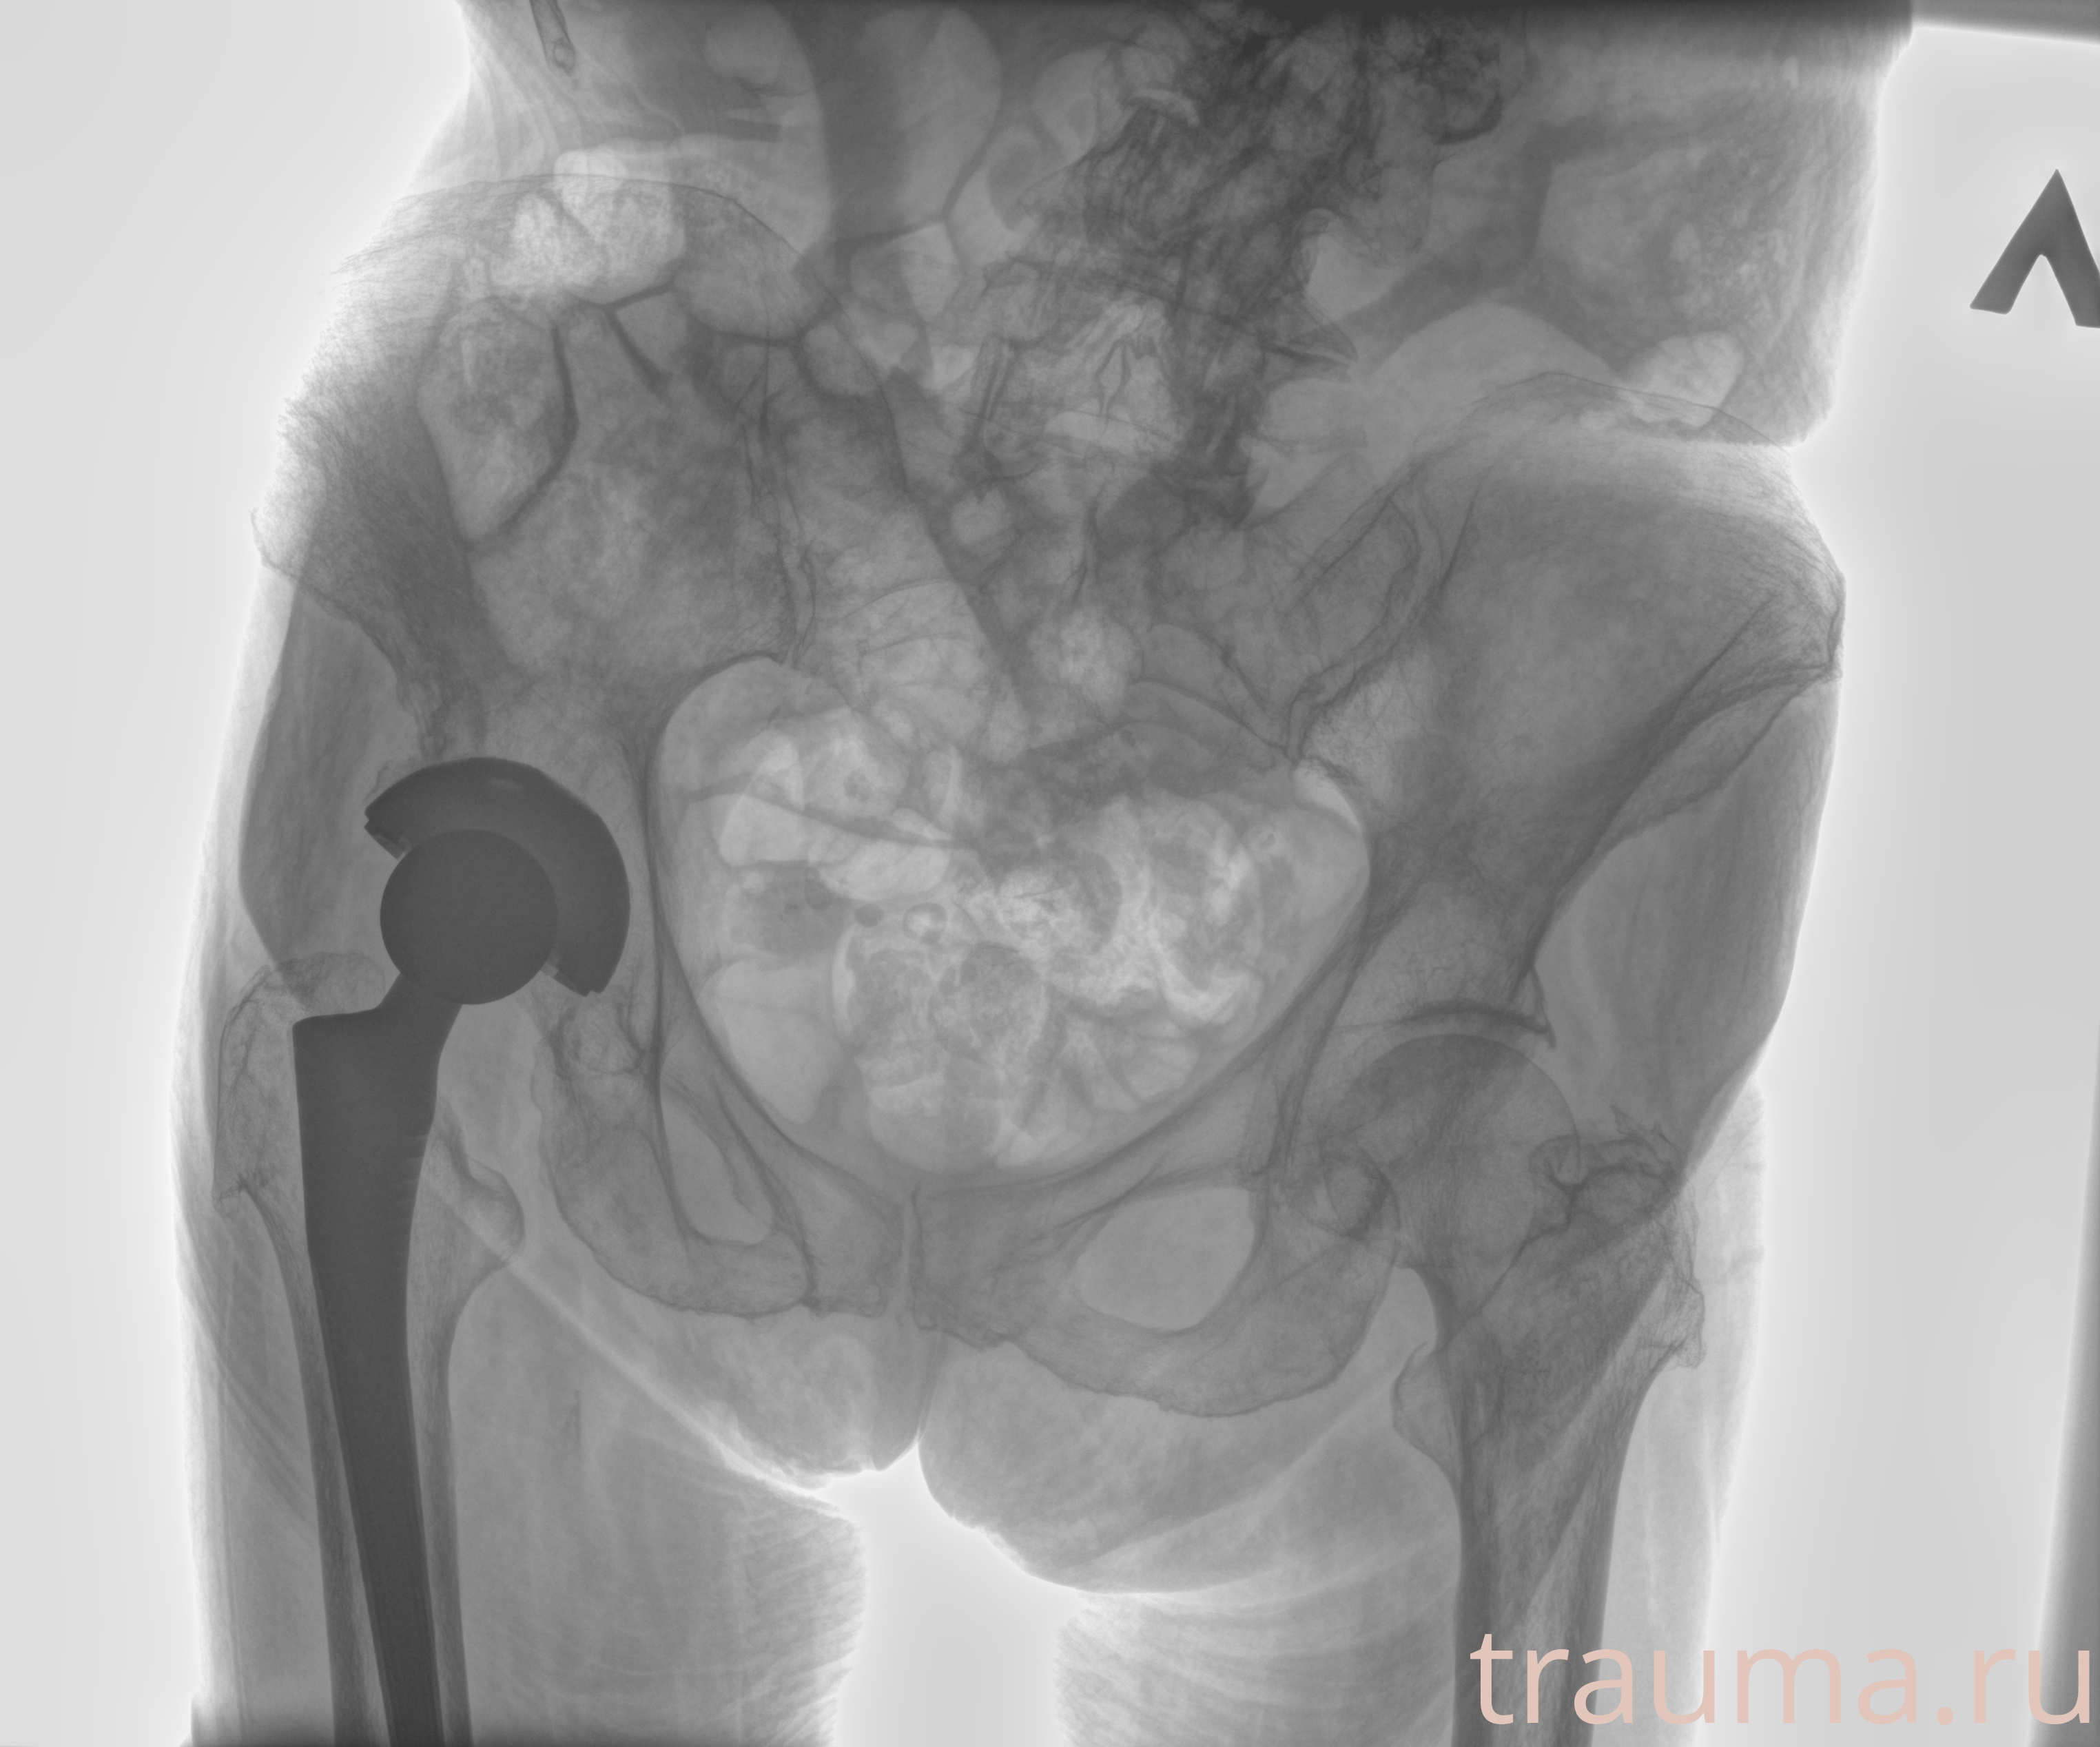

Рентгенограммы

Рентген на дому: по вашему адресу приезжает врач-рентгенолог, травматолог-ортопед с мобильным рентгеновским аппаратом, проводит диагностику травмы или заболевания, делает необходимые рентгенограммы, дает рекомендации по дальнейшему лечению. Получить качественные снимки в домашних условиях возможно благодаря уникальной методике, разработанной МосРентген Центром для института  Склифосовского